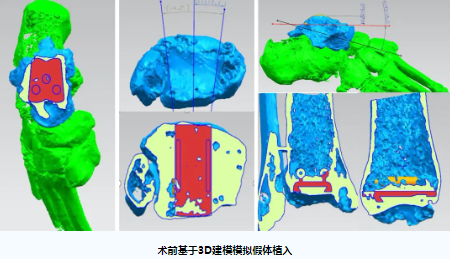

钟环主任医师团队综合分析,患者想既要解决疼痛问题又能较好地保留踝关节的活动度,实施右侧全踝关节置术是最佳的选择。根据既往我院开展的踝关节置换手术经验,高先生的骨骼条件并无严重畸形,整个手术过程可以通过3D打印术前规划和辅助截骨获得更加精准的植入效果。最终,关节外科团队与患者及家属充分沟通,决定应用3D打印技术为高先生实施标准化假体的右侧全踝关节置换术。随后,钟环主任与手术团队成员在计算机3D模型前进行反复模拟演练,充分考虑标准化踝关节置换手术技术实施过程中的关键节点和术中潜在风险,准备了多套预案以应对术中情况的变化。

人工踝关节置换术是足踝外科领域难度最高的手术之一,标准化的人工关节假体设计精巧,手术操作复杂,手术失败的风险高,对主刀医生的操作有着极高的要求。据文献报道,不少患者因置换手术失败或术后效果不满意而不得不再次行踝关节融合手术进行补救。目前,粤西尚未见独立开展标准化人工踝关节置换术的报道,本次踝关节置换手术取得了良好的治疗效果,得益于关节外科团队巧妙运用了数字骨科3D术前规划技术为高先生进行详尽的计划,有效地避免了许多常见的技术陷阱,本次手术的成功实施,标志着我院足踝外科的人工关节置换技术达到了省内先进水平。